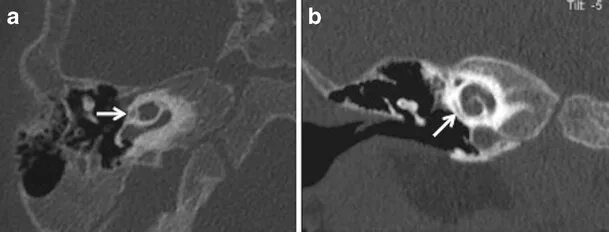

Кохлеарный отосклероз